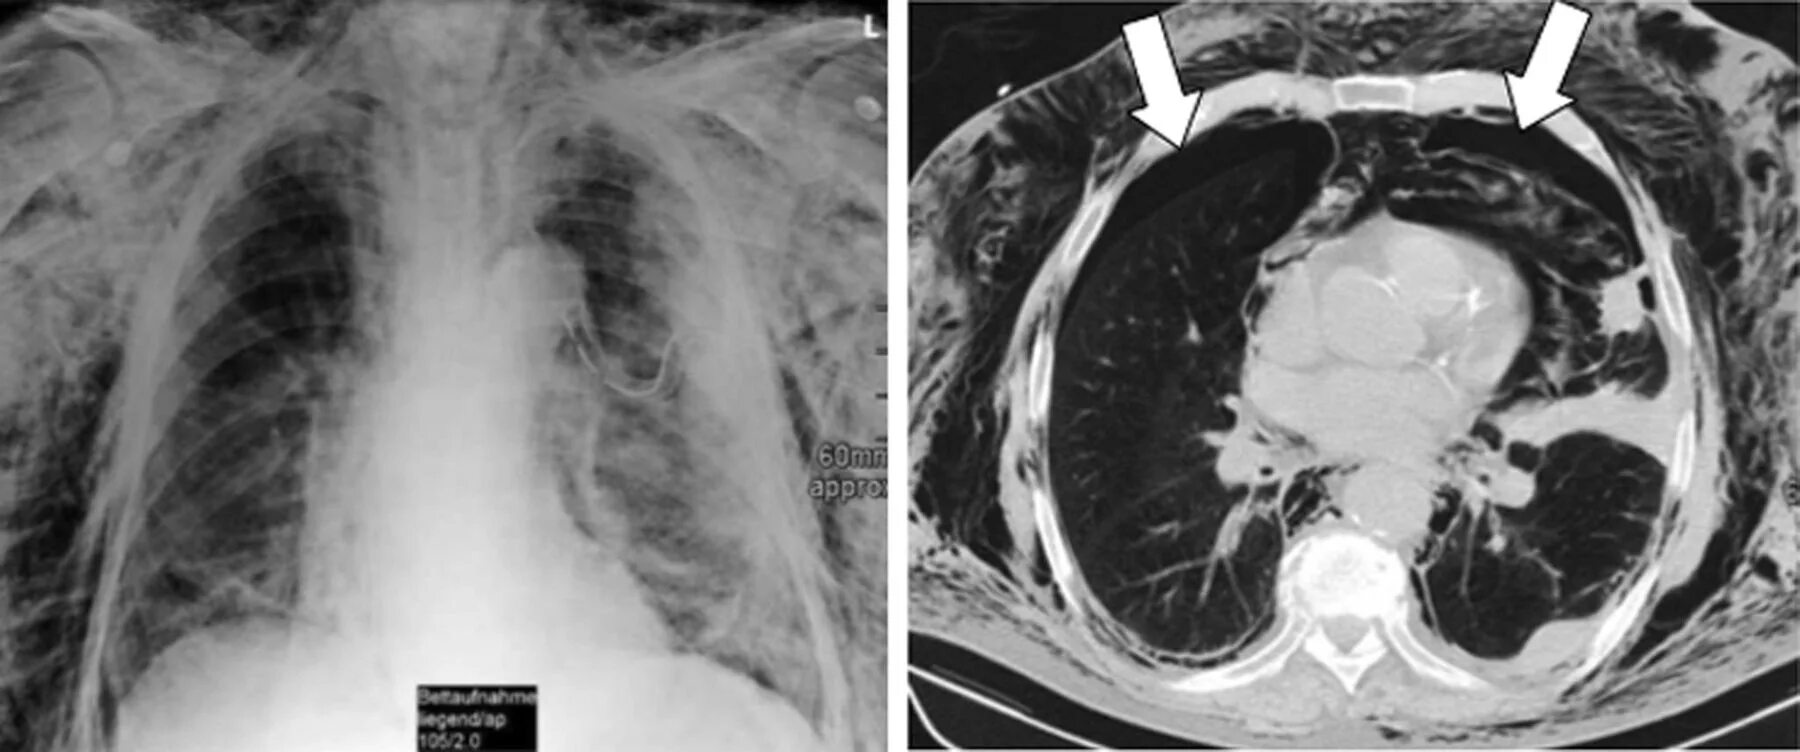

Эмфизема мягких